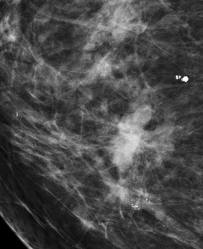

Digital Mammography

Technology - Hologic Selenia Digital Mammography

The Selenia full-field digital mammography system provides exceptional image quality and improves the efficiency of exams, shortening each patient's examination time.